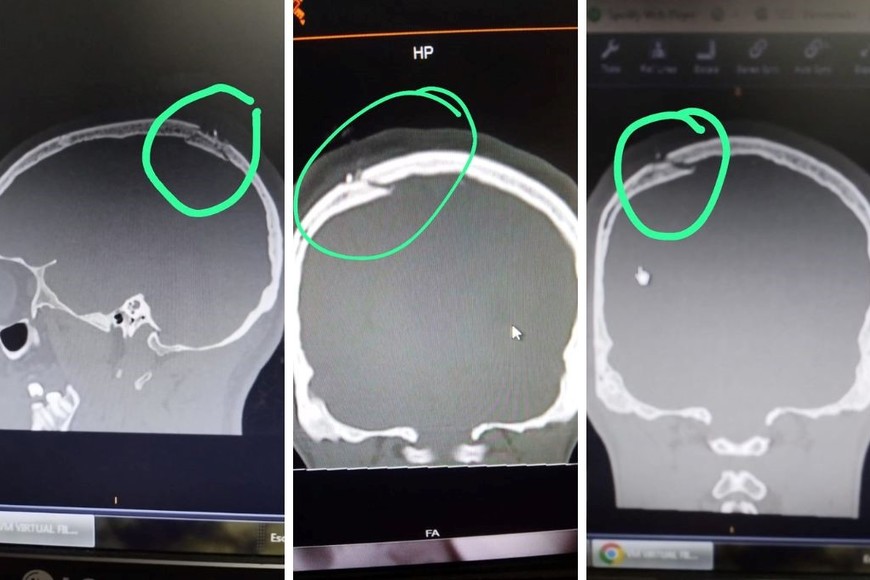

Las placas donde se observa con claridad la lesión en el cráneo.

Emiliano (24) recibió un fuerte golpe en su cabeza por tres delincuentes que le robaron su bicicleta. En el hospital Cullen le dijeron que solo tenía una herida cortante y que se dirija al Samco de Santo Tomé para suturar. Tras una tomografía en la ART se constató que tenía fractura de cráneo.

“La cabeza de mi hijo. No hay fractura me dijo el médico del Cullen... No solo eso sino que no lo suturaron y nos mandaron de vuelta al Samco de Santo Tomé para que lo suturen allá. Ineptos, inhumanos, cero empatía... Cada vez peor… El informe del doctor Mateo Ignacio Riera donde dice que no hay fractura ni lesión ósea y que se traslada al Samco para suturar... Que Dios nos libre de esas manos…”

Pero cerca del mediodía del lunes Emiliano fue examinado por un médico de la ART que ordenó una resonancia, la que reveló una fractura de cráneo.